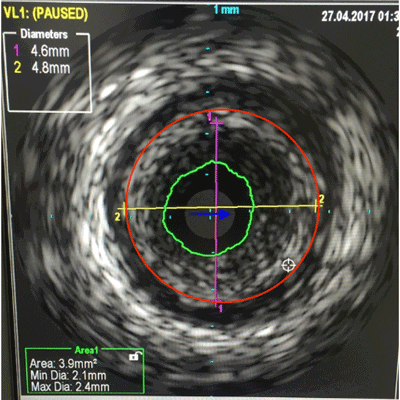

A 38 year old male with chest discomfort had a strongly positive stress perfusion scan. His coronary angiography showed a blocked lad artery.

This subset is called a Chroic Total Occlusion or a CTO. A hard tipped wire was used to cross the blockage and a Special Intravascular Ultrasound (IVUS) was used to get an image the blockage and to assess the size of the artery.

Based on this IVUS image, a large stent was deployed and the artery was opened and blood flow was restored.